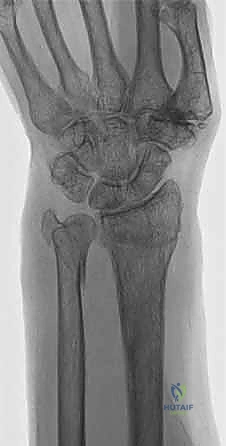

1. الأشعة السينية (X-rays): بوضعيات متعددة (أمامية خلفية، وجانبية دقيقة). الوضعية الجانبية الحقيقية (True Lateral) حاسمة لاكتشاف أي خلع جزئي في المفصل (DRUJ).

2. الأشعة المقطعية ثلاثية الأبعاد (3D CT Scan): تُستخدم في الكسور المفتتة أو كسور رأس الزند المفصلية المعقدة، حيث تعطي خريطة دقيقة للجراح قبل الدخول لغرفة العمليات.

3. الرنين المغناطيسي (MRI): يُطلب عند الاشتباه القوي بوجود تمزقات في الأربطة والمركب الغضروفي (TFCC) التي لا تظهر في الأشعة السينية.

الأشعة المقطعية توفر تفاصيل دقيقة للكسر